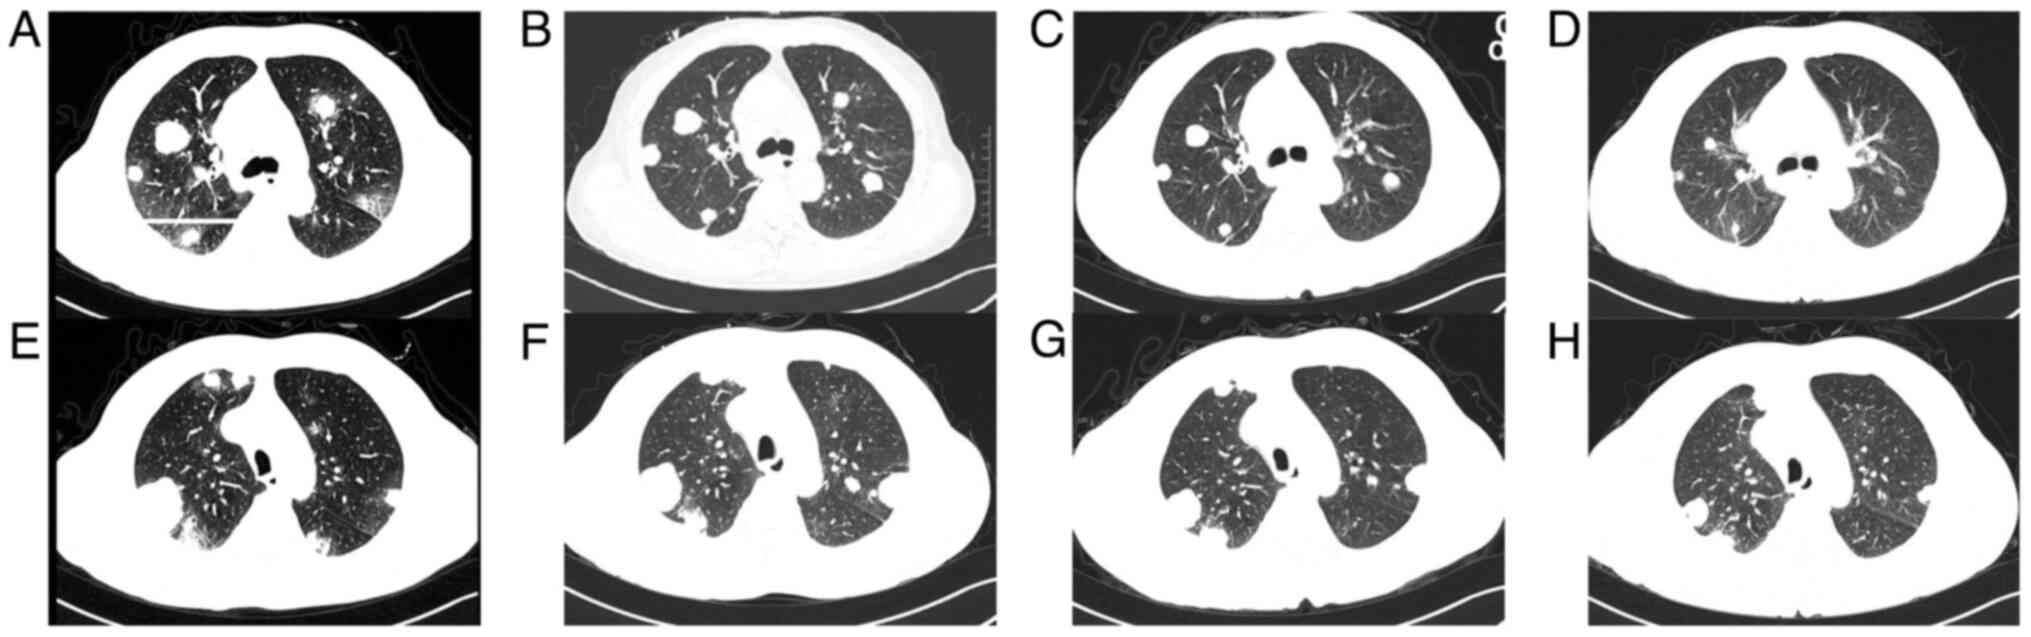

The patient then received chemotherapy with etoposide and cisplatin (EP). Considering the high-volume of lung metastases of the male patient, bleomycin was excluded due to its pulmonary toxicity. HCG levels decreased continuously after each cycle of chemotherapy (Fig. 3), and the patient no longer complained of haemoptysis. However, after two cycles of chemotherapy, a brain MRI revealed new malignant lesions in the (Fig. 4A) left frontal lobe, (Fig. 4D) left ventricle and (Fig. 4G) left occipital lobe. Meanwhile, chest CT showed that some lung lesions had decreased in size, while others had increased in size (Fig. 5A, B, E and F). Stereotactic body radiotherapy (SBRT) of the intracranial lesions was then administered (a dose of 40 Gy delivered in 10 fractions) with concurrent chemotherapy of the third cycle. As the patient suffered from severe bone marrow suppression during chemotherapy, the male patient refused further HDCT or ASCT after six cycles of EP therapy. Although the HCG levels decreased continuously and most of the metastases decreased in size, the treatment was suspended for 6 weeks. Although immunotherapy was recommended, the patient demanded to return to Tibet with oral medication for economic and physical reasons. Comprehensive assessment was then arranged. Laboratory results of the tumour markers showed that HCG was elevated to 572.9 U/l and LDH was 195 U/l. The brain MRI showed stable encephalic lesions with slight reduction in size (Fig. 4A-I). The chest CT revealed that most of the pulmonary lesions were decreasing in size, while others were slightly increasing in size (Fig. 5A-H). The patient returned to Tibet with oral etoposide. Notably, 4 weeks later the patient agreed to receive immunotherapy of sintilimab along with oral etoposide. However, without therapeutic evaluation the condition of the patient deteriorated 2 weeks later. The patient developed respiratory failure accompanied by massive haemoptysis and eventually succumbed 2 days later at home.

Figure 5

Tumour response to treatment. Computed tomography scans of the metastatic masses in the lungs (A and E) before treatment, (B and F) after two cycles, (C and G) after four cycles, (D and H) after six cycles of etoposide and cisplatin chemotherapy. Some pulmonary lesions decreased in size while others enlarged in size after two cycles of chemotherapy. In the last four cycles of chemotherapy, most of the pulmonary metastases continued to decrease in size.